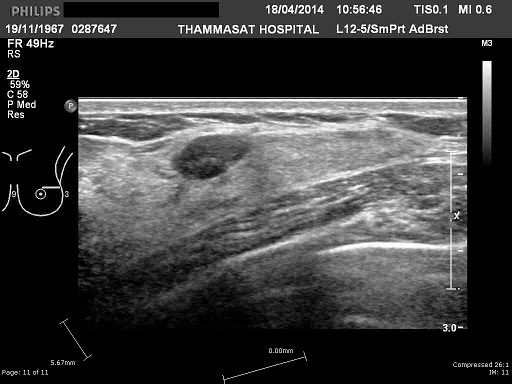

An example of the input image: